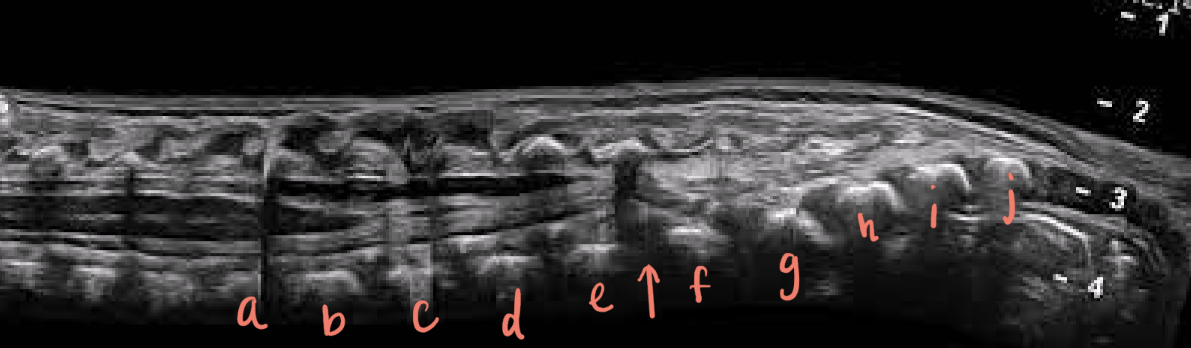

a

L1

b

L2

c

L3

d

L4

e

L5

f

S1

g

S2

h

S3

i

S4

J

S5

arrow

filum terminale